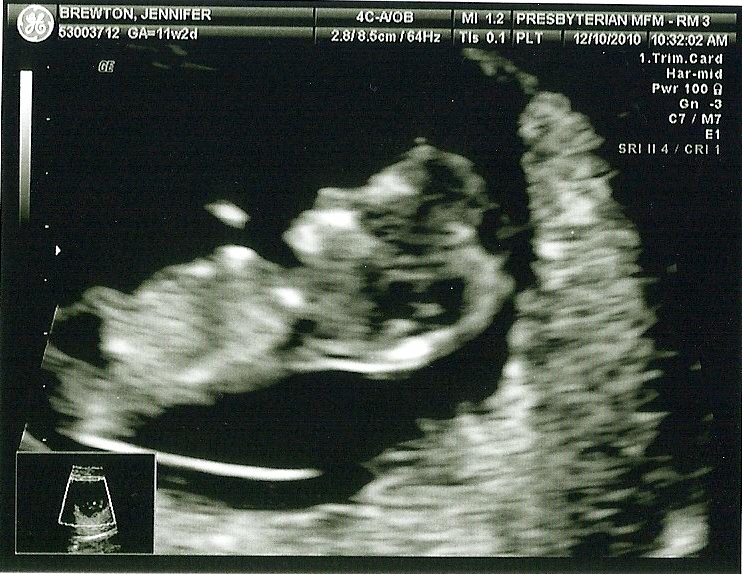

On December 10th, Dan and I went down to the city to have another ultrasound done, and I was a ball of nerves once again. At this point I was 11 weeks 2 days and I was excited to see the baby, but worried that the same thing that happened during my last pregnancy may happen again. I was feeling a little more symptomatic this pregnancy, I was very hungry and having a bit of nausea. I felt like I was always tired and I had had a bit of a stretching feeling in my lower abdoman (which they say are your ligamants stretching to accomodate your growing uterus) so I felt like everything was going well, but I just didn’t know, and I was getting anxiety which was not healthy for me or for the baby. Dan, once again, was my rock, and assured me time and again that I was fine and always reminded me to think positively. I don’t know what I would do without him, and I am grateful every day for him and his optimistic outlook on life. He sat next to me in the ultrasound room, held my hand and made light of everything so I would calm down and relax. As soon as the wand was on my belly and I saw the image of our baby it was like a huge weight was lifted off of my chest, and I could breath again. It was much bigger than last time, and actually looked like a baby and we were immediately able to see the flicker of the heart and hear it beating 168 bpm, fast and strong. We promised our Mom’s that we would text them as soon as we had any news so Dan was on that right away, and everyone was happy!

It was amazing to see the head and the body, and the arms and legs moving all over the place (Definitely its’ fathers child, can’t sit still ) Everytime the ultrasound tech would try to take a picture the baby would make a jerky movement and kind of blur the image so we got a lot of pictures. The Dr. came in checked me again and the baby had flipped to the other side! It was the neatest thing!! He also confirmed that everything looked great and that the baby was developing exactly as it should be.